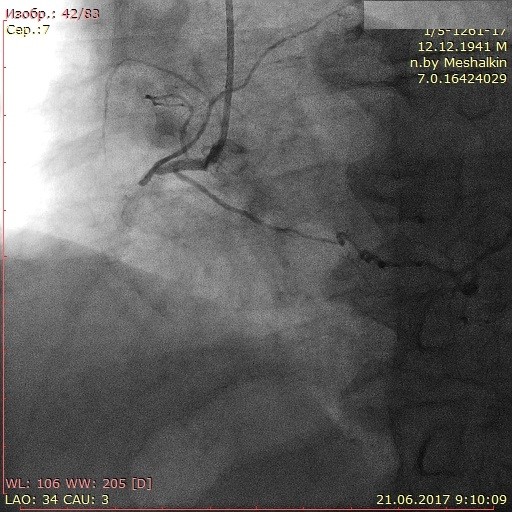

Материал и методы: 90 пациентов с трехсосудистым поражением коронарного русла и обязательным наличием окклюзии правой коронарной артерии (ПКА) в зависимости от варианта развития коллатерального крвоснабжения были разделены на две группы: в первую группу вошли 44 пациента (44%) с наличем коллатералей I и II степени градации по Rentrop, во вторую группу – 46 пациентов (56%) с наличием коллатералей 3 градации по Rentrop. Проанализированы данные перфузионной сцинтиграфии, эхокардиографии и тканевой допплерографии.

Результаты: Выявлено ухудшение перфузии миокарда по нижней стенке у пациента из второй группы при незначимом дефекте перфузии у пациента из первой группы. СДП в 1 группе составил 9,8±3,5%, во второй группе – 4,1±1,7%. При сравнении показателей тканевой допплерографии более значимое изменение продольной деформации в области нижней стенки левого желудочка выявлено в группе с плохим коллатеральным руслом: – 4,1±2,6, во 2 группе: – 6,8±2,7. При оценке сегментарной сократимости нижней стенки левого желудочка выявлено меньшее количество сегментов гипокинеза в группе 2.

Заключение: Хроническая окклюзия коронарной артерии со слабым коллатеральным кровоснабжением сопровождается худшими показателями локальных перфузии и функции миокарда. При хорошем развитии коллатералей, несмотря на незначимые нарушения перфузии миокарда в покое, имеются отчетливые стресс-дефекты перфузии и нарушения локальной сократимости миокарда.